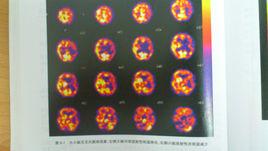

交叉性小腦失聯絡是指一側大腦皮質有局限性放射性分布減低或缺損,同時對側小腦放射性分布亦明顯減低,多見於慢性腦血管病。

的診斷。可以發現交叉性小腦失聯絡徵象、過度灌注等現象,對臨床不能用CT和...